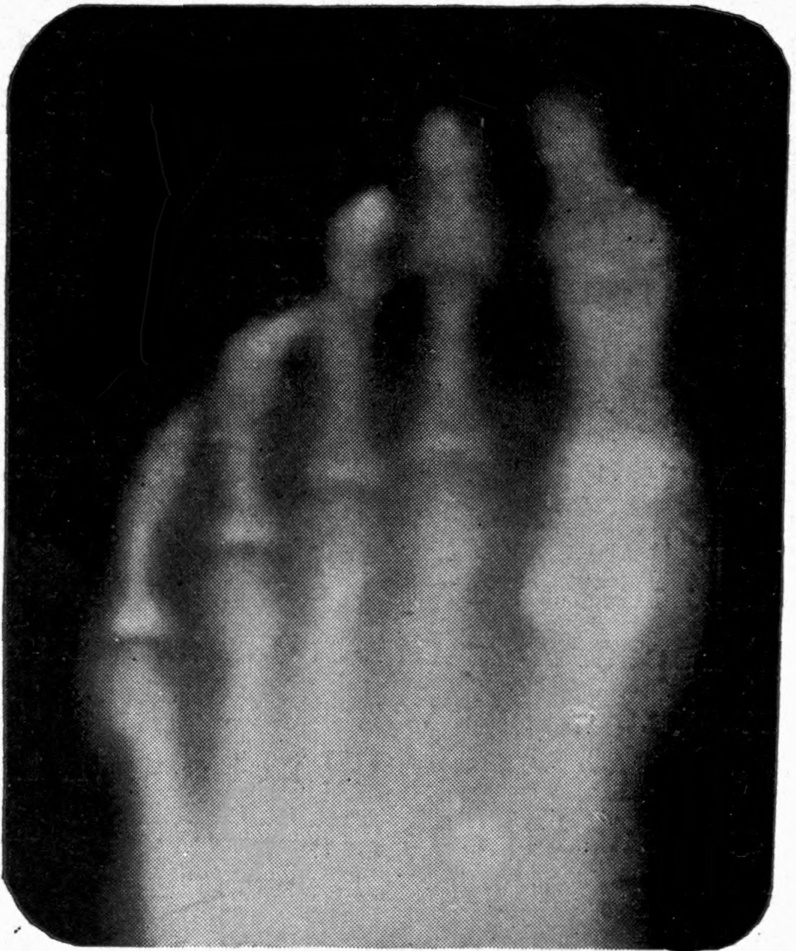

205. Application of X-rays in Dentistry. Morton

117a. Molecular Sciagraphs in a Vacuum Tube. Hammer and Fleming